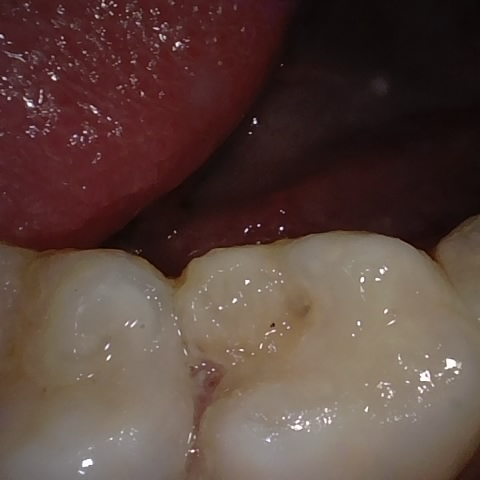

Annotated as "Good"